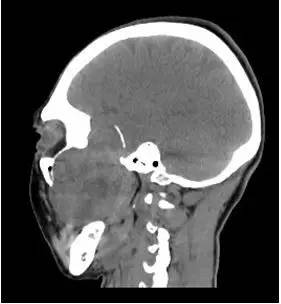

CT平扫矢状位重建

解析:本病例为中颅窝至颞下窝沟通性病变,对周围骨质主要呈膨胀压迫性改变,伴囊变、出血。